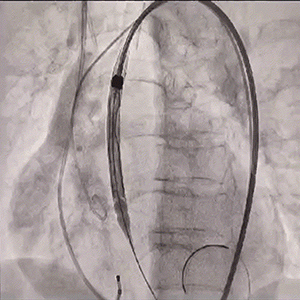

瓣膜一次稳定释放

瓣膜稳定脱钩